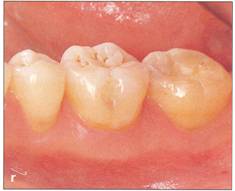

Fi 545e45f gs 5-4r to 5-4t One year 6 months after transplantation. The donor tooth is restored with composite resin. |

Root canal treatment in transplanted teeth Root canal treatment is necessary in the fully developed donor tooth because healing of the pulp cannot be expected after apical closure (see Fi 545e45f gs 5-1s, 5-41, 5-7j, 5-7k, 5-lOr, and 5-lOs). In the case of an impacted donor tooth, RCT is performed 2 weeks after the transplantation. After preparing the root canals, an interim dressing of calcium hydroxide is placed in the canals. About 2 months later, the calcium hydroxide is replaced with gutta percha and sealer.19 The reason RCT is started 2 weeks after the transplantation is that earlier RCT may affect the attachment around the transplanted tooth and obturation material may damage the periodontal ligament. The advantage of using calcium hydroxide before final obturation is twofold: (1) if the tooth is not fully formed, the calcium hydroxide will promote apical closure and (2) the calcium hydroxide is an excellent antiseptic that will keep the root canal system free from bacterial contamination during the important attachment phase of healing (see Fi 545e45f gs 5-1s, 5-41, and 5-8hh). Root canal treatment performed extra orally at the time of transplantation is both time- and cost-effective. However, there is the risk of damage to the periodontalligament during the procedure, so extraoral RCT is not recommended unless the periodontal ligament can be kept intact during the procedure, which is very uncertain.21 Healing of the pulp is expected with transplanted developing teeth (see Fi 545e45f gs 5-2 and 5-9). Closure of the apex and positive response to electric pulp tests are expected. The roots should continue to develop (see Fi 545e45f gs 5-9k to 5-90). The pulp should be monitered for healing with transplanted teeth at developmental stage 6. Root canal treatment should be started immediately if inflammatory root resorption is suspected (see Fi 545e45f gs 5-60 and 5-8gg), or if irreversible pulpitis is diagnosed. Once closure of the apex with hard tissue after apexification (see Fi 545e45f g 3-37) is confirmed, obturation with sealer and gutta percha is performed (see Fi 545e45f gs 5-3m and 5-8ii). |